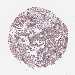

Colorectal cancer

Rectum adenocarcinoma